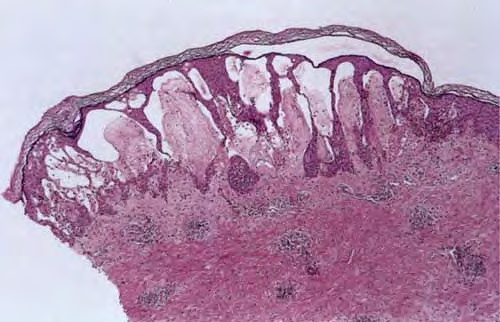

Atlas of skin histopathology

spongiotic-dermatitis